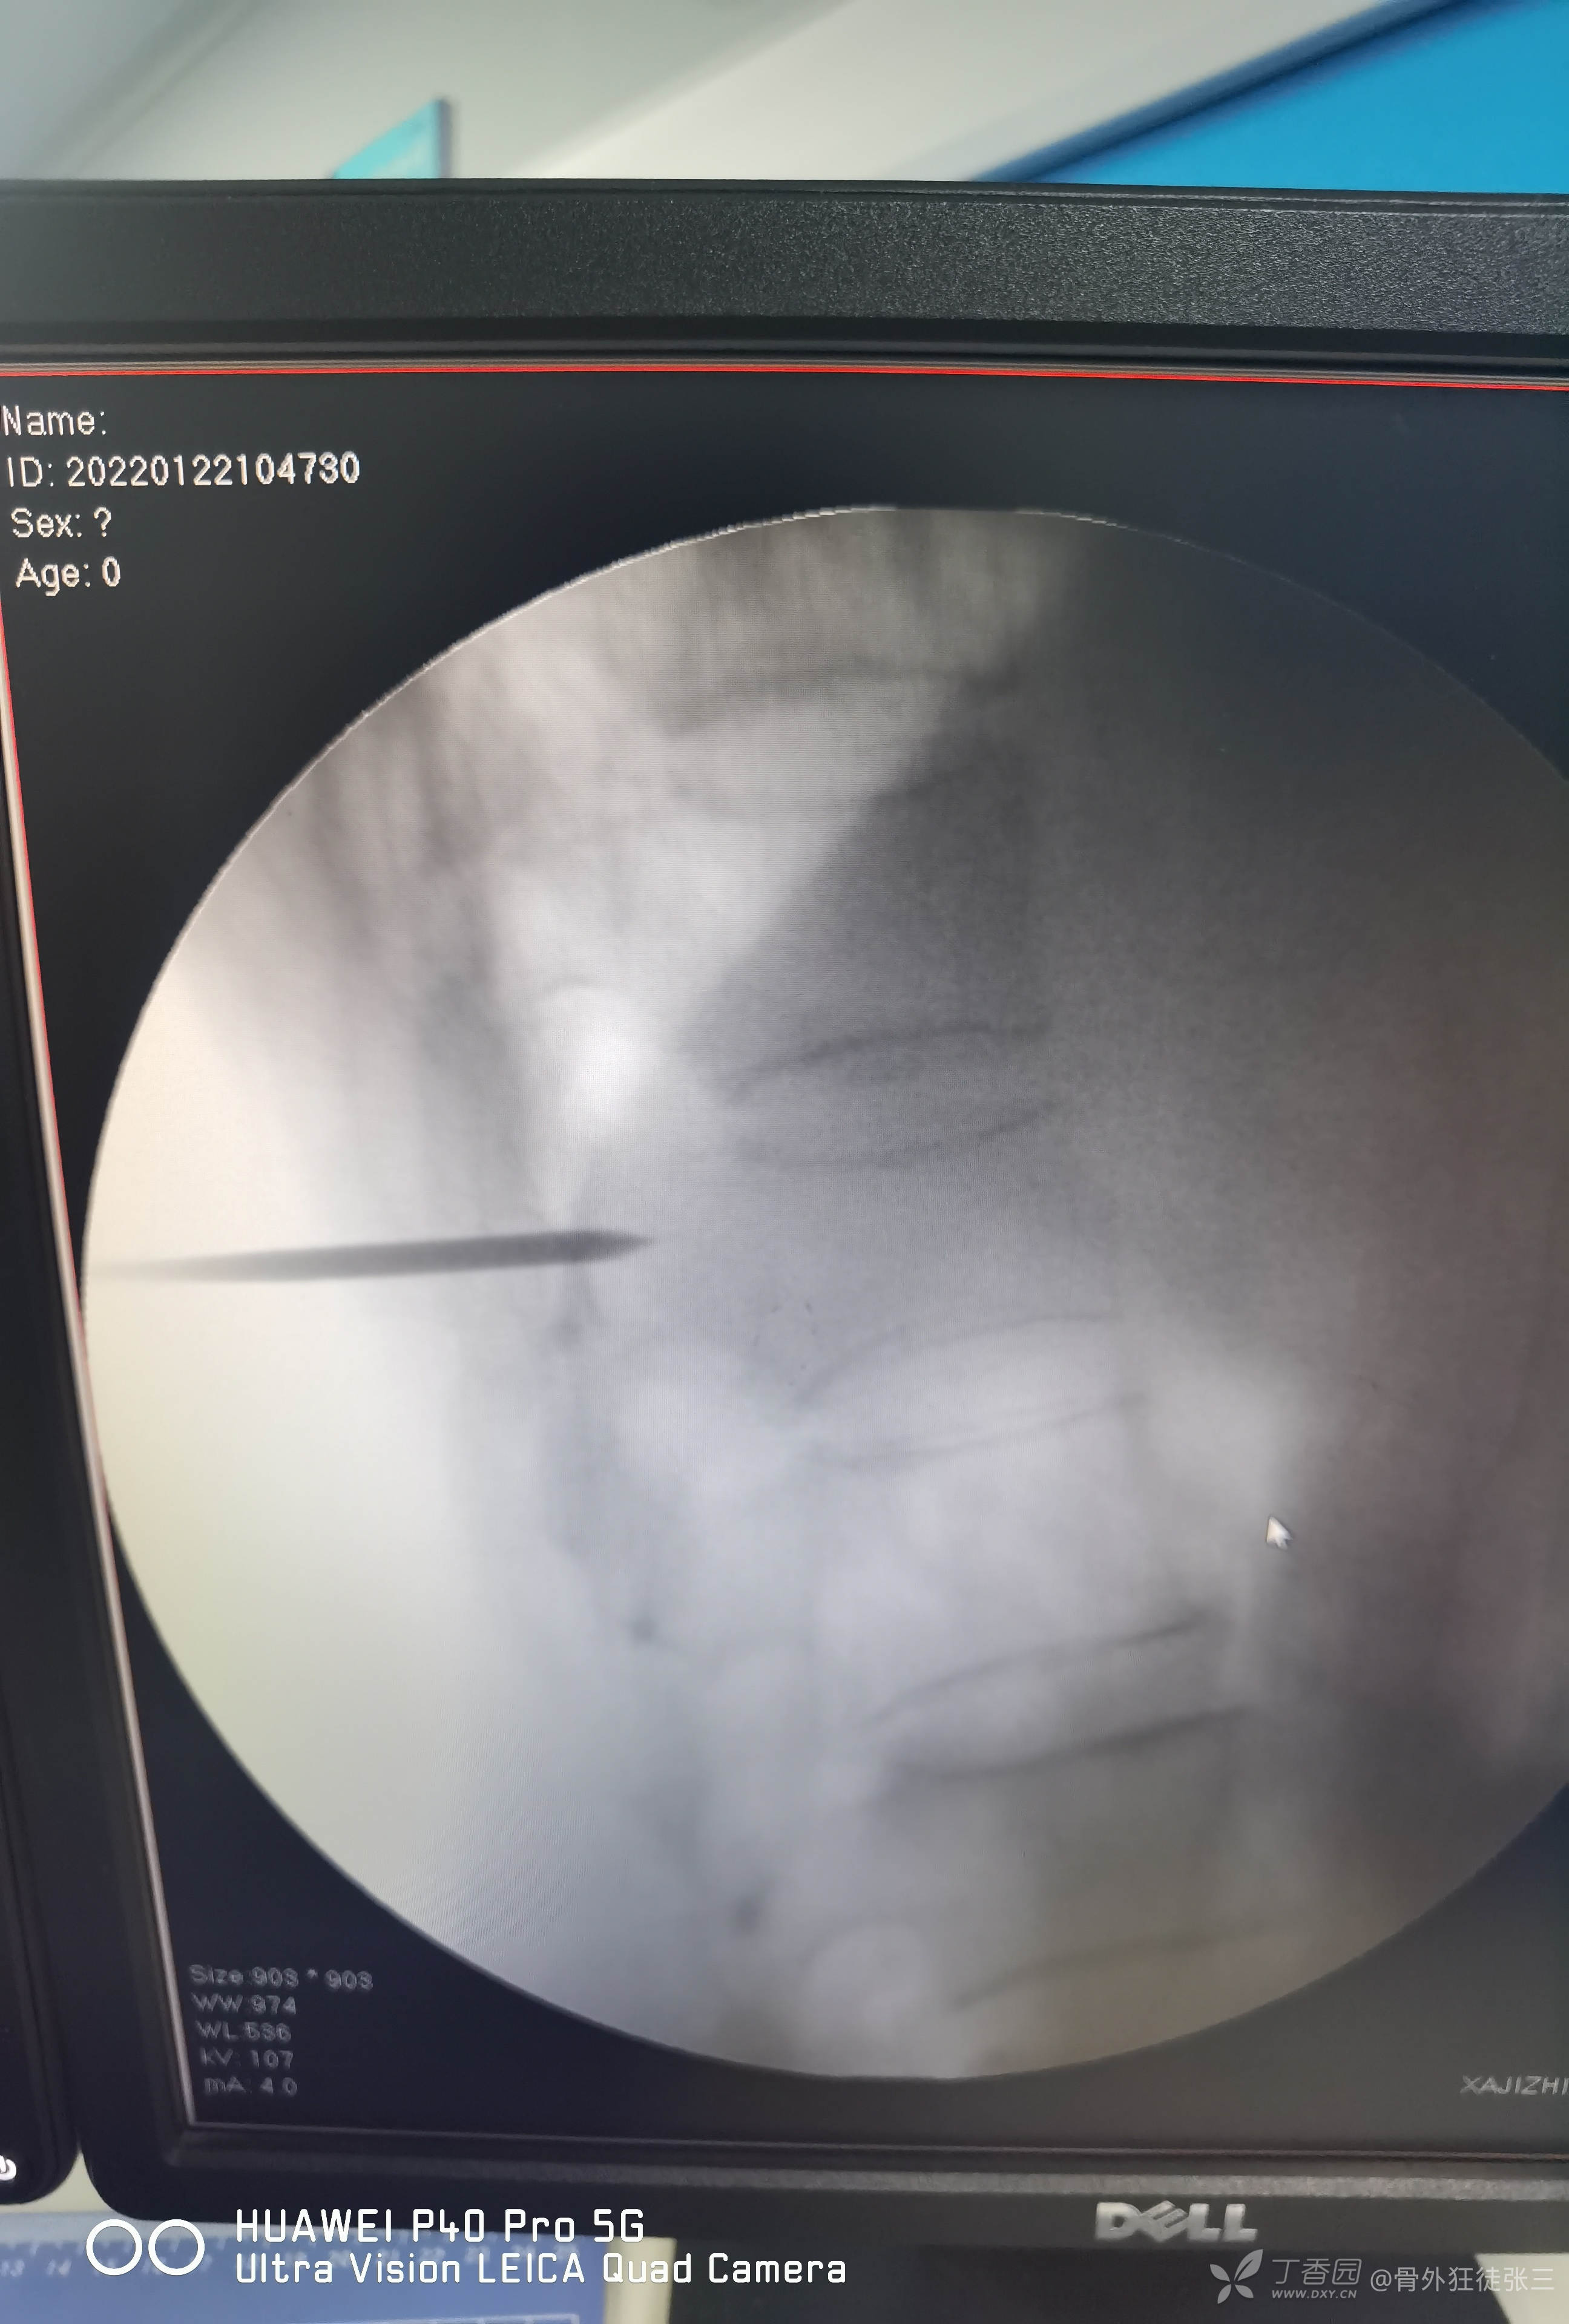

术前讨论后行经皮穿刺椎体成形术。

术前定位

一共注入4ml骨水泥